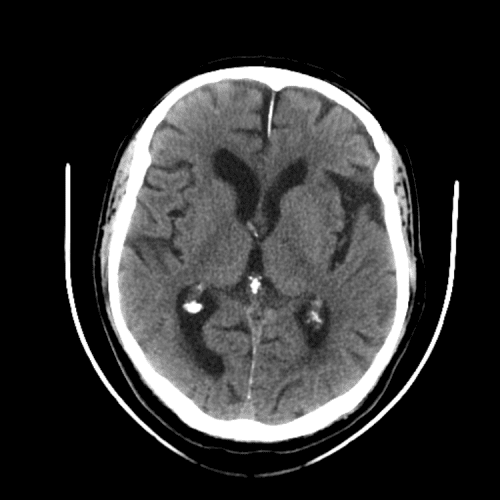

ACA and MCA territory infarct

PCA infarct

PICA infarct

Internal capsule lacunar infarct

Superior cerebellar artery infarct